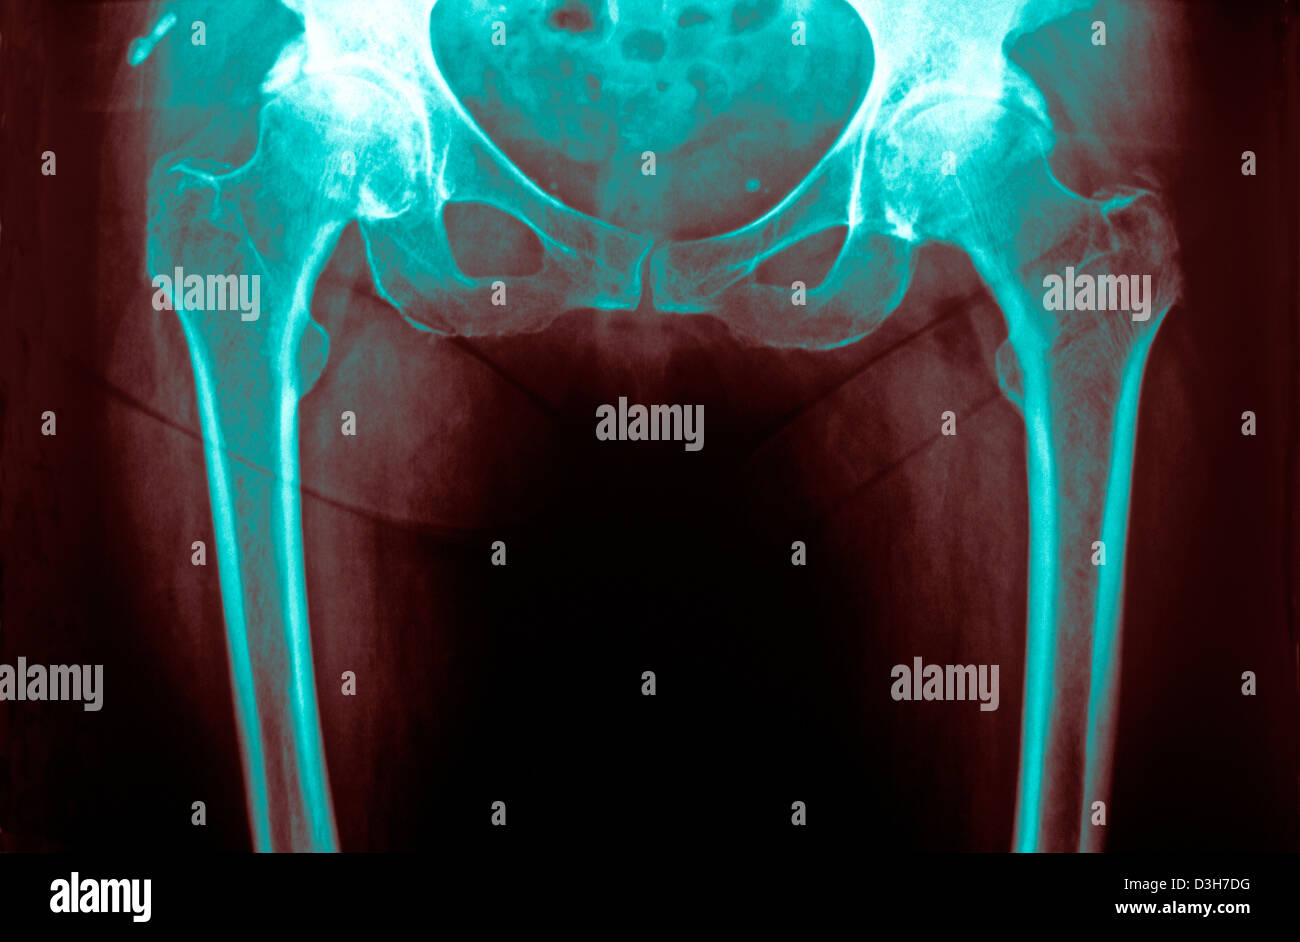

HIP OSTEOARTHRITIS, XRAY Stock Photo Alamy Hip Osteoarthritis X Ray Radiopaedia The diagnosis of oa is based on a combination of radiographic findings of joint degeneration and. Typical osteoarthritis findings include joint space narrowing, osteophytes, subchondral sclerosis, and subchondral cysts. Currently, the most common radiographic. Different grading schemes are described for plain radiographs of the hip: Hip osteoarthritis is degenerative disease of the hip joint that causes progressive loss of articular. Hip Osteoarthritis X Ray Radiopaedia.